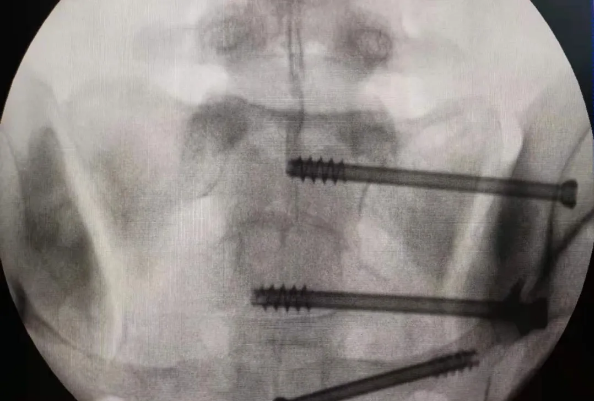

在南昌市第一医院廖琦教授带领下,由创伤骨科团队借助天玑®骨科手术机器人为患者“量身定做”最理想、最安全的教科书般的通道,完美安全微创完成手术,并且手术时间明显缩短,真正做到“指哪儿打哪儿”!更让患者放心的是,天玑®骨科手术机器人的“稳定手”机械臂进行精准定位,不用反复探寻。

由于天玑®骨科手术机器人的精准及高效,可以使手术时间明显缩短,因此在骨盆骨折手术后,在廖琦教授指导下,脊柱外科团队利用天玑®骨科手术机器人同样为20岁女性腰椎骨折患者“量身定做”最理想、最安全的教科书般的通道,完美安全微创完成手术,手术不仅时间缩短,并且出血和透视减少。

➁ 机械臂就是天玑®骨科手术机器人的“稳定手”,运动灵活、操作稳定,能达到亚毫米的精度;